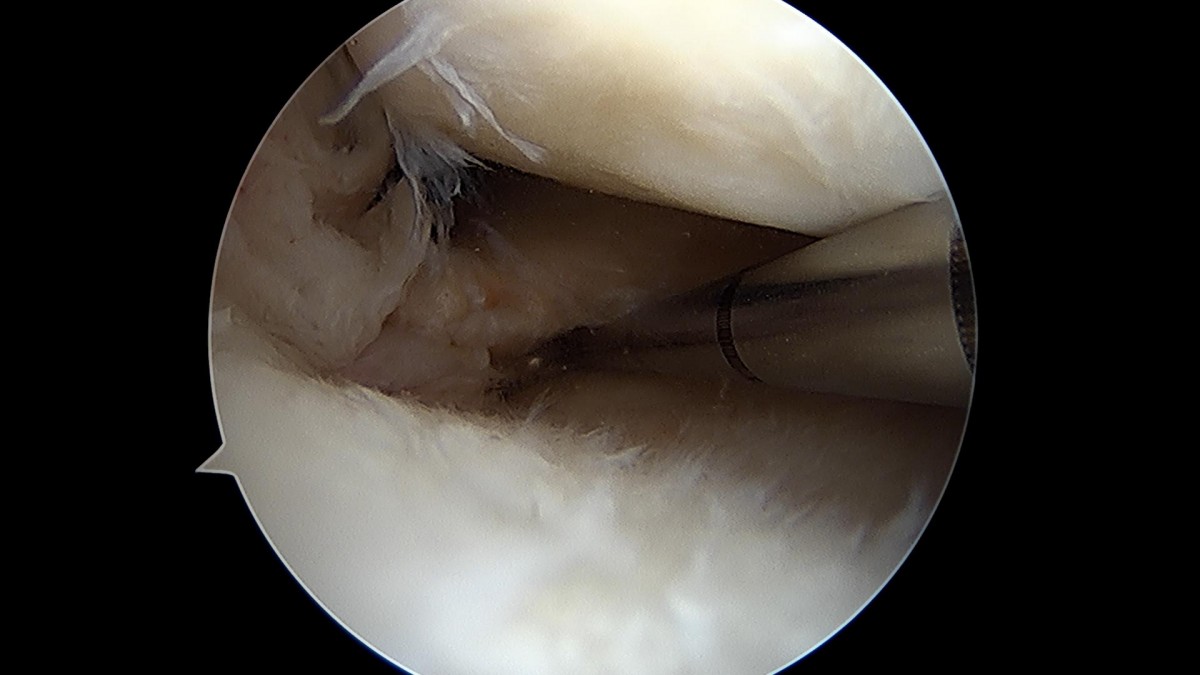

배우한원장님 무릎 반월상 연골판 파열 수술 (782)염광O 환자

작성자 최고관리자 댓글 0건 조회 1,058회 작성일 22-02-23 12:40